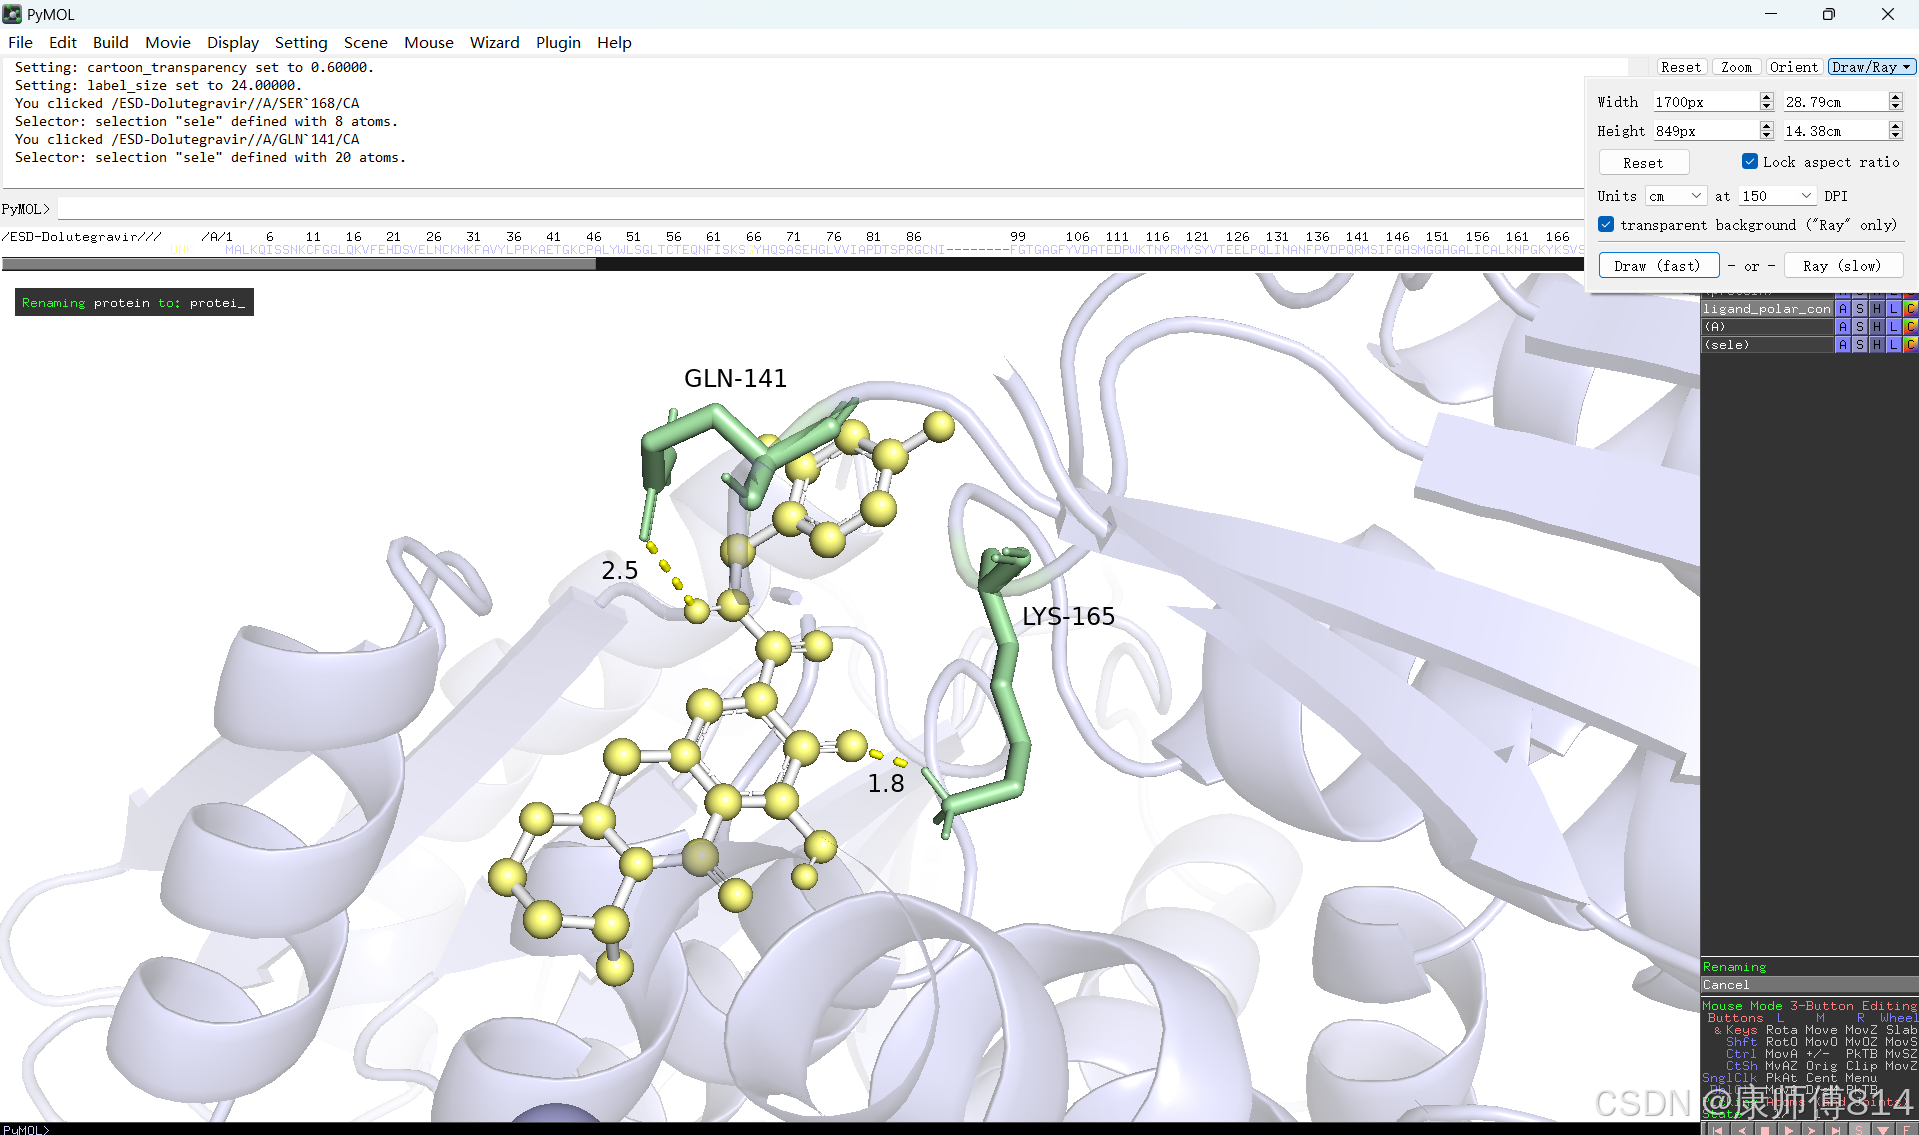

#修改好后就可以导出了,点击右上角Draw,选择合适的格式导出即可

结果演示